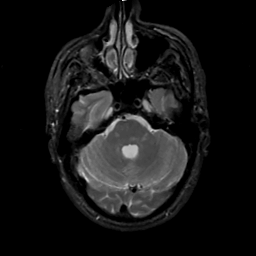

MR Study #2, February 17, 1991 -- Slice #13

[Home][Help][Clinical][Tour 1][Tour 2] Slice 13